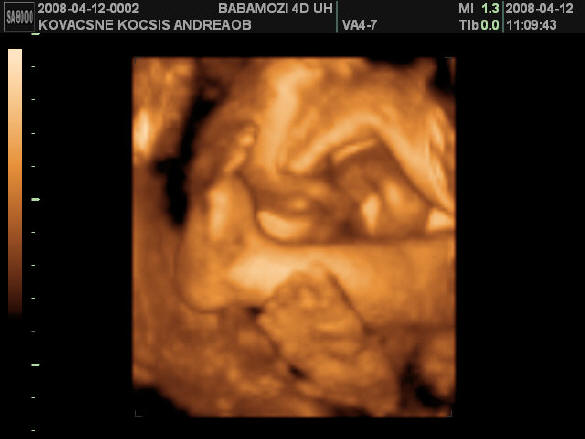

31 hetes